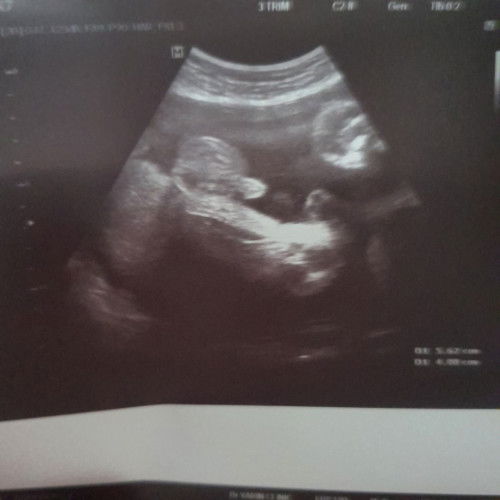

รู้ว่าหม่าม้าอยากได้ผู้ชาย ซาวด์ทุกรอบ โชว์ทุกรอบ ล่าสุดคุณหมอบอกว่า ไข่ใหญ่ไปนะ